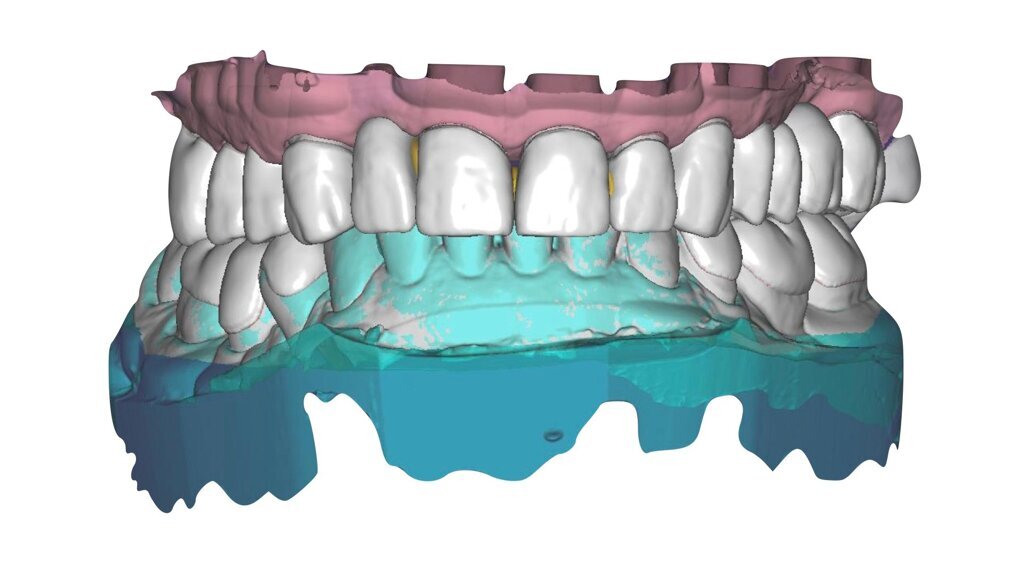

I modelli sono così importati in corretta posizione spaziale tramite il modulo exocad Virtual Articulator (Fig. 25). Non avendo a disposizione nel CAD l’analogo virtuale dell’articolatore Reference SL, viene impostato il sistema virtuale SAM, che usa lo stesso piano di riferimento axio-orbitale e geometria sovrapponibile al Reference SL. Per la programmazione virtuale dei parametri funzionali dell’articolatore si riesegue l’output dall’axiografia elettronica con Gamma Dental per SAM (Fig. 26). Si procede perciò ora con la modellazione CAD della ceratura mantenendo il riferimento dato dal piano occlusale individuato dai coni di centrica scansiti con l’articolatore (Fig. 27). L’articolatore virtuale consente una prima verifica dei rapporti occlusali tra gli elementi e un abbozzo di funzionalizzazione delle cuspidi con strumenti virtuali dinamici, che permette di arrivare ad un CAD design vicino alla morfologia ricercata (Figg. 28-33). Il modellato è ora fresato in cera Yeti Dental al CAM con fresatore VHF Cam5-S1 ed i denti in cera, tutti singolarmente sfilabili, sono posizionati sui modelli eseguiti con stampa 3D.

Il paziente utilizza questi secondi provvisori per otto settimane, durante le quali conferma la buona integrazione dei restauri e la soddisfacente funzione occlusale. Ciò è verificato con l’esecuzione di una nuova axiografia elettronica che già a due settimane dalla consegna evidenzia una buona risposta muscolare al nuovo design occlusale ed alla nuova postura mandibolare in TRP (Figg. 43-46). Provvediamo infine alle impronte per la costruzione dei manufatti definitivi in Zirconia-ceramica. I modelli sono scansiti in laboratorio con inEos X5 (Dentsply Sirona) su exocad (Figg. 47-49), ed una seconda scansione viene eseguita con i provvisori del Paziente posizionati sui modelli (Figg. 50-52). Il CAD consente di eseguire un matching fra le due scansioni, per cui i secondi provvisori utilizzati in TRP, con funzione occlusale sequenziale già completamente programmata, sono utilizzati per definire le morfologie dentali definitive di tutti gli elementi da restaurare (Figg. 53, 54) secondo il rapporto intermascellare definito (Figg. 55-58). Si esegue quindi fresatura al CAM della protesi definitiva in zirconia (Figg. 59, 60), la stratificazione e finitura ed infine la consegna al Paziente con cementazione in Panavia V5 (Figg. 61-65).